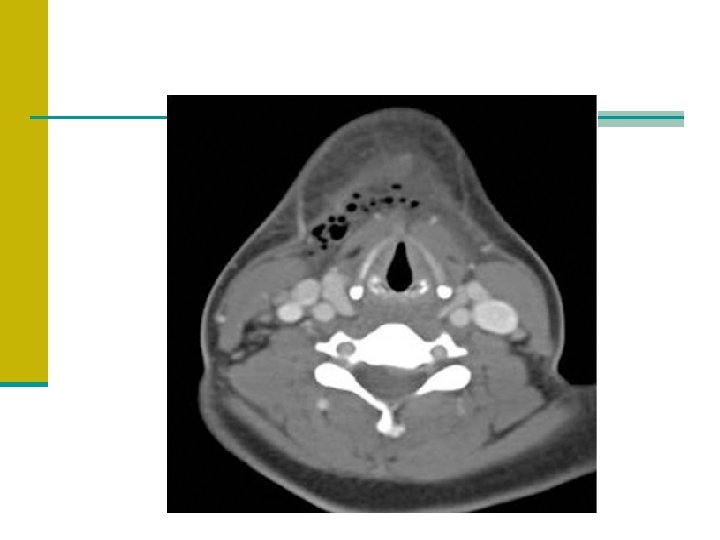

RFA tanı n Boynun kontrastlı BT’si gold standarttır. -Erken dönemde reaktif , nonsüpüratif ödem, doku planlarında hafif yağlanma, çizgisel sıvı, minimal kitle etkisi gözlenir. -Kontrast tutulumu yoktur. -Apse merkezinde düşük atenüasyon ve etrafında halka tarzında kontrast tutan nekrotik dokulardan oluşur. n Orta derece servikal ekstansiyon ile inspirasyon sırasında çekilen boynun lat yumuşak doku radyografisi retrofarengeal duvarın protruzyonunu ve kalınlaşmasını gösterebilir. *****Havayolu sıkıntısı olan hasta BT’ye gözlemcisiz gönderilmemelidir.

RFA